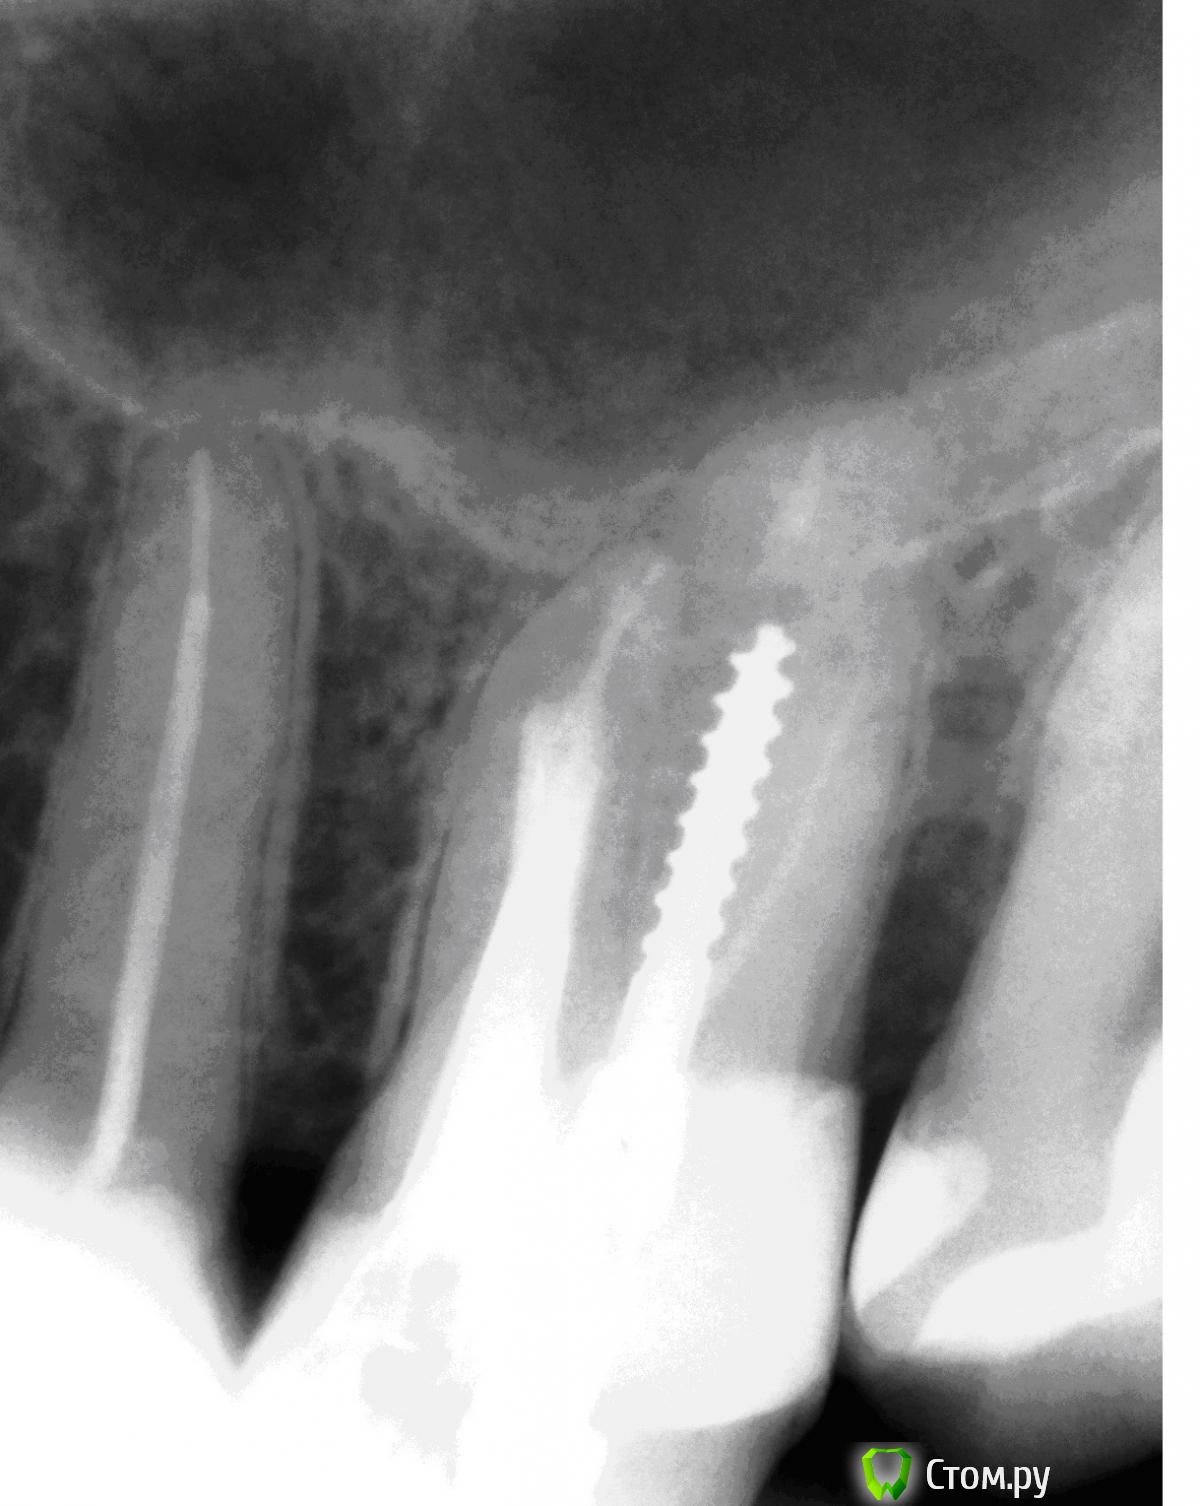

Каплан Опубликовано 30 января, 2014 Поделиться Опубликовано 30 января, 2014 когда распломбируете, картинка должна выглядеть как-то так... http://s020.radikal.ru/i716/1401/fb/530548708dc6.jpg пс. Паша (M@estro), стянул у тебя картинку из темы, извини )) 2 Ссылка на комментарий

Rumyanceff Опубликовано 30 января, 2014 Автор Поделиться Опубликовано 30 января, 2014 когда распломбируете, картинка должна выглядеть как-то так... http://s020.radikal.ru/i716/1401/fb/530548708dc6.jpg пс. Паша (M@estro), стянул у тебя картинку из темы, извини ))Да, это наиболее предпочтительный вариант Ссылка на комментарий